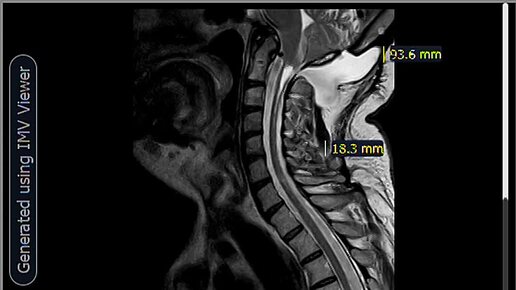

МРТ- Менингоцеле